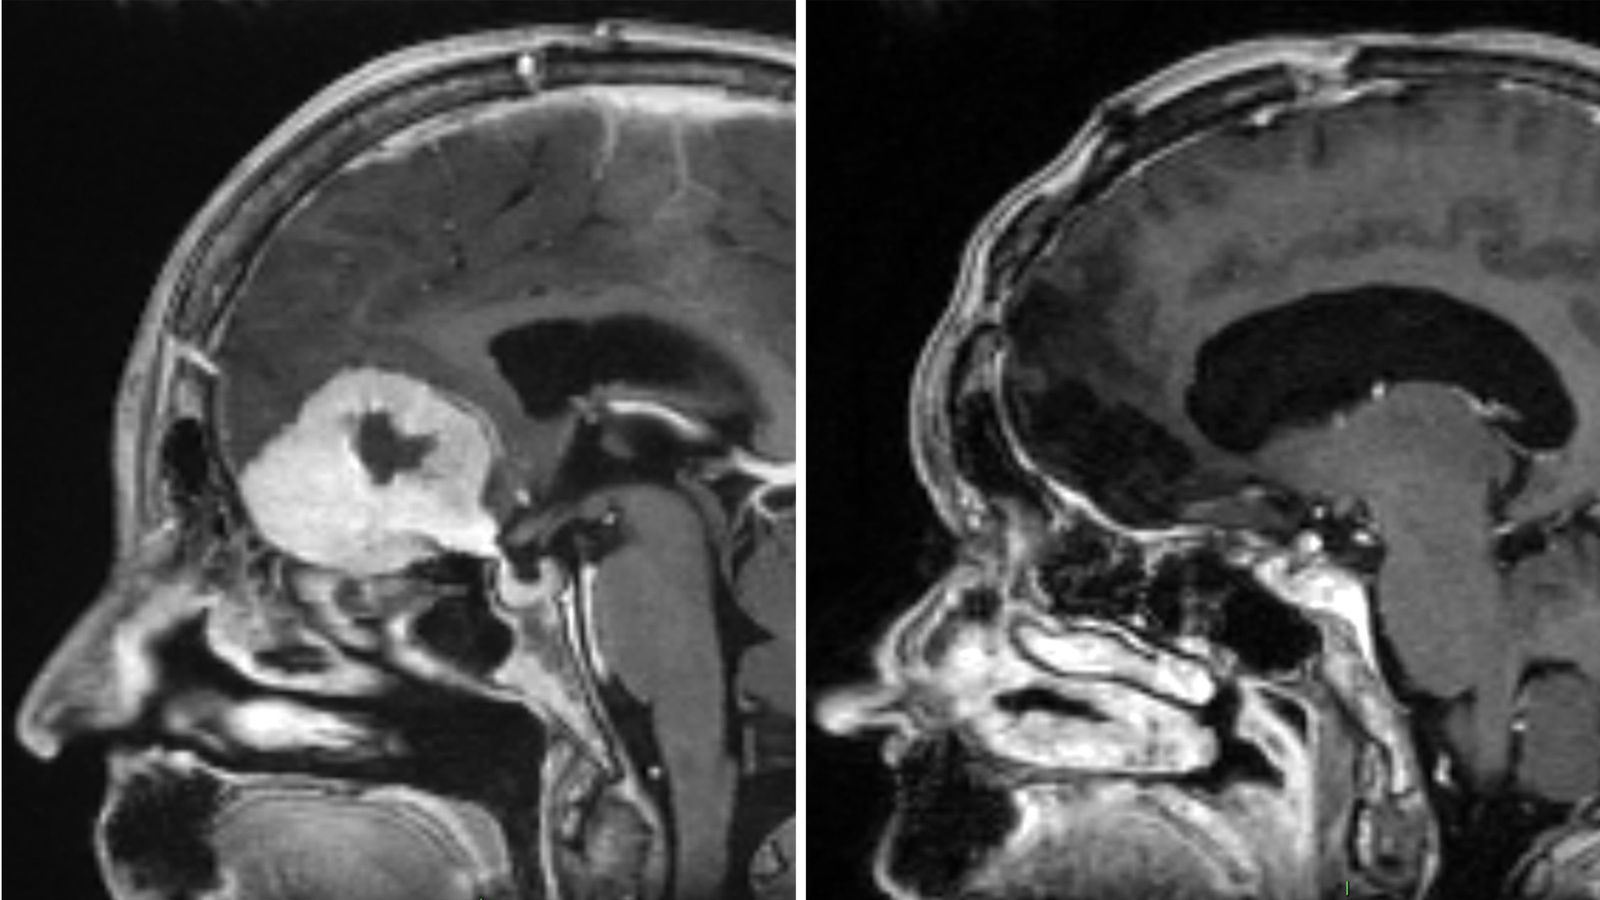

A surgeon is removing brain tumours “the size of large apples” through patients’ eyebrows, in what is believed to be a world first.

Consultant neurosurgeon Anastasios Giamouriadis, based in Aberdeen, has adapted an existing technique to remove the growths, leaving patients with only a small scar and black eye.

Mr Giamouriadis who works for NHS Grampian said this type of surgery is not new, but he has modified it to give him “more space, through the eyebrow” allowing him “to remove very big brain tumours”.

The technique is “a game-changer and much less invasive”, he said. “Traditionally people would be left with scars across their full forehead, we avoid that with this method.”

Doreen Adams, 75, underwent a craniotomy to remove a tumour abroad before later undergoing the eyebrow method last year – known as the Modified Eyebrow Keyhole SupraOrbital Approach for Brain Tumours.